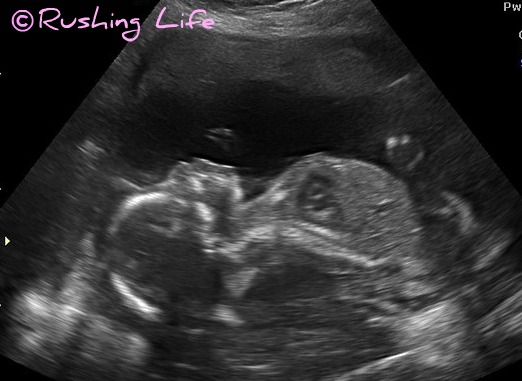

Well... meet Bimmer. (Again.)

There are girl parts involved now.

And while Puff started to feel like he was going to have a heart attack in the ultrasound room, apparently he is excited. As am I. It definitely makes the entire situation much more real and purposeful. I am growing something someone inside me and SHE depends on me. Like, completely. Yeah, this shit is pretty scary.